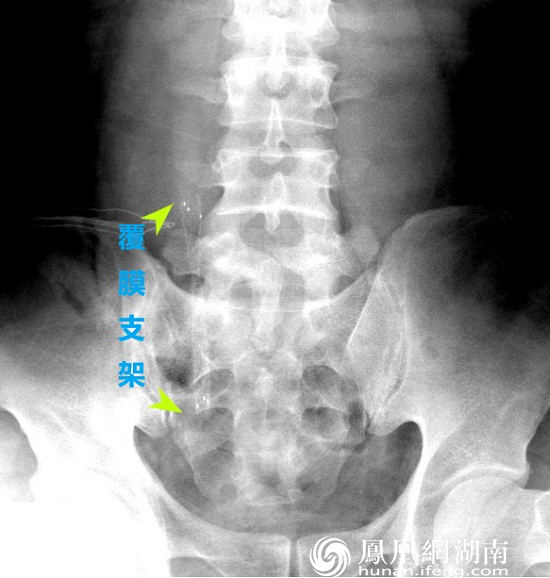

X线摄片显示覆膜金属支架已置入患者右侧输尿管

图左:绿色箭头示传统的输尿管支架管(其头端在肾脏内,尾端在膀胱内,因其两端卷曲形似英文字“J”而取名双J管)图右:绿色箭头示覆膜支架